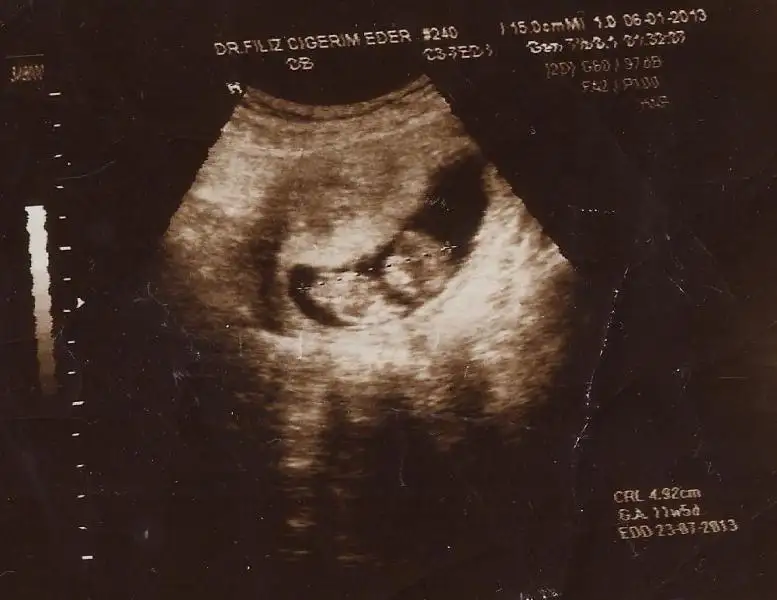

dayanamadım,kızlar bende yorum bekliyorum sizlerden.ilk resim 11 hafta 3 günlük dr.erkek olcak dedi.ben pek inanmadım. 2.resim13 hafta 3 günlük,dr.muz bütün hislerim erkek olcakmış diyor dedi,yine inanmadım nedense.çok erken diye belki.yada kıza çok alışkınım hep içimden bir prensesim olacakmış gibi geliyor.4 yaşında dünya güzeli pirensesim var.rabbim hayırlısını nasip etsin.banada birrr yorum sevgili arkadaşlarım.bu işin ehli olmuş orkidem arkadaşım,senden de yorum bekliyorum.tabi musait olduğunda.....